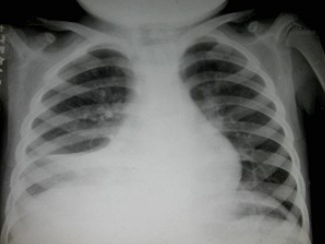

男,8岁,高热达38.5℃三天,如图所示,最可能的诊断为()

B.原发综合征